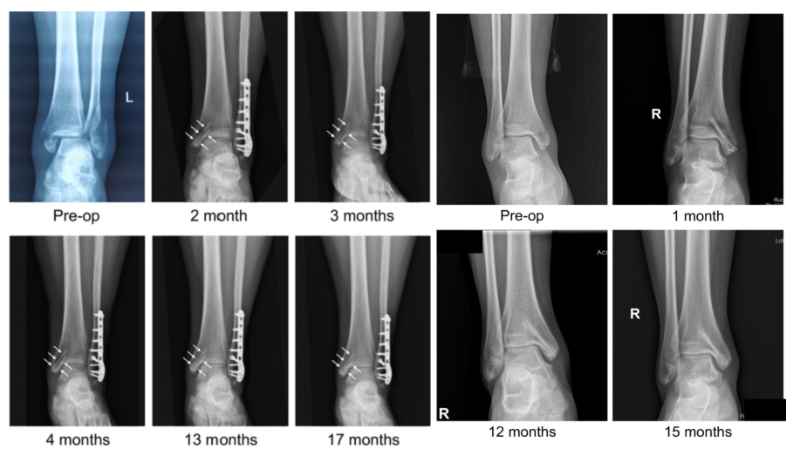

近日,國際骨科臨床轉化期刊《Journal of Orthopaedic Translation》在線發(fā)表了由上海交大戴尅戎院士、郝永強教授團隊和丁文江院士、袁廣銀教授團隊合作發(fā)表的可降解鎂合金骨釘1-2年的臨床試驗觀察結果,所有患者術后內踝骨折愈合,功能恢復。研究證實了可降解鎂合金螺釘治療內踝骨折的臨床療效及其生物安全性,為全降解鎂合金植入物等高端醫(yī)療器械進一步的臨床推廣應用奠定了堅實基礎,相關成果以“Effectiveness and safety of biodegradable Mg-Nd-Zn-Zr alloy screws for the treatment of medial malleolar fractures”為題在線發(fā)表于Journal of Orthopaedic Translation,27 (2021) 96–100。這是國內首個可降解醫(yī)用鎂合金臨床試驗的公開報道,也是國際首款含有功能涂層的可降解鎂合金骨釘?shù)呐R床試驗結果的公開報道,具有里程碑意義。

醫(yī)用鎂合金骨內植物臨床試驗研究突破性進展(圖1)

醫(yī)用鎂合金骨內植物臨床試驗研究突破性進展(圖2)